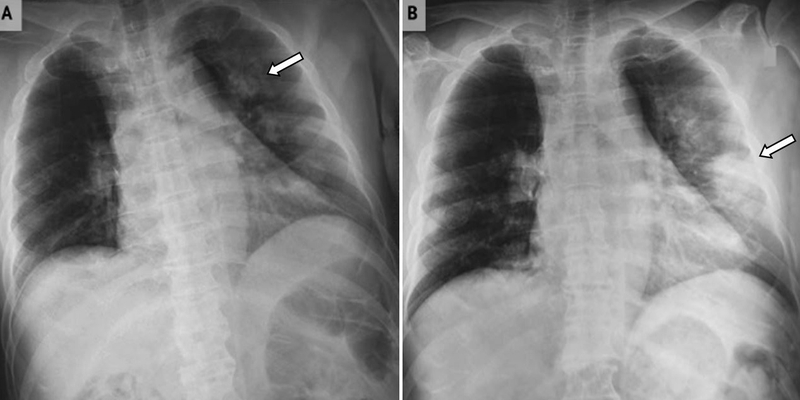

Bệnh phổi trắng không phải là tên gọi của một bệnh cụ thể mà là thuật ngữ thường dùng trong chẩn đoán hình ảnh, đặc biệt trên phim X-quang hoặc CT ngực. Khi quan sát thấy vùng phổi mất đi màu đen đặc trưng của khí và thay bằng hình ảnh trắng đục, bác sĩ sẽ nghĩ đến tình trạng phổi bị lấp đầy bởi dịch, mủ, tế bào viêm hoặc mô xơ. Đây là dấu hiệu cảnh báo những bệnh lý hô hấp nghiêm trọng như viêm phổi nặng, phù phổi cấp hoặc xơ phổi tiến triển.

Bệnh phổi trắng sống được bao lâu?

“Bệnh phổi trắng sống được bao lâu?” là thắc mắc phổ biến của nhiều người khi nhận được chẩn đoán liên quan đến tình trạng này. Trên thực tế, không có một con số cụ thể áp dụng cho tất cả trường hợp, bởi tiên lượng sống phụ thuộc rất lớn vào nguyên nhân gây ra hiện tượng “phổi trắng” trên phim chụp.

Nếu tình trạng này xuất phát từ các bệnh lý nghiêm trọng như ung thư phổi giai đoạn muộn, thời gian sống có thể chỉ kéo dài trong vài tháng nếu không đáp ứng điều trị. Ngược lại, với những bệnh mạn tính như xơ phổi, người bệnh vẫn có thể duy trì cuộc sống trong nhiều năm nếu được theo dõi và kiểm soát tốt. Trong trường hợp nguyên nhân là viêm phổi cấp tính, đặc biệt khi được phát hiện sớm và điều trị đúng cách, khả năng hồi phục hoàn toàn là hoàn toàn có thể.